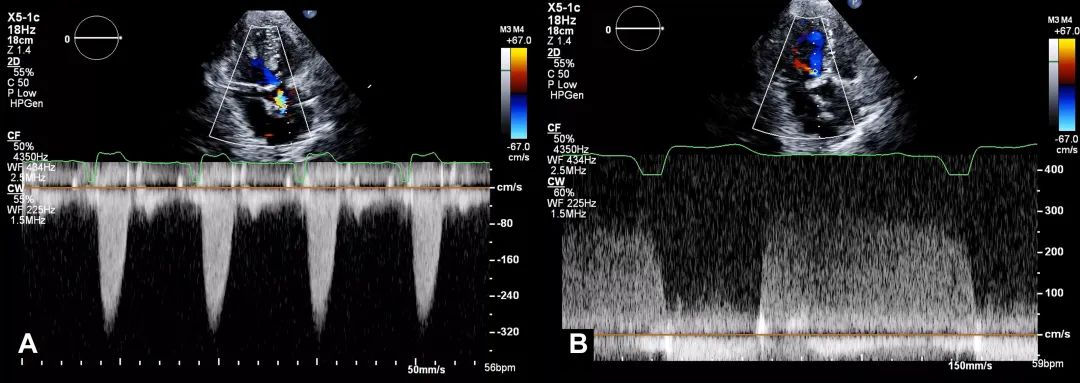

8、心尖五腔心切面:将连续多普勒(continuous-wave Doppler,CW)取样线对准主动脉瓣血流方向,测量主动脉瓣峰值流速和跨瓣压差,并评估是否存在主动脉瓣反流。测量主动脉瓣峰值流速波形(图9)。

图9. 心尖五腔心切面连续多普勒评估

心尖五腔心切面:将连续多普勒取样线对准主动脉瓣血流方向,测量主动脉瓣峰值流速(A)和跨瓣压差,并评估主动脉瓣反流(B)。

11、心尖三腔心切面: 将连续多普勒取样线对准主动脉瓣血流方向,获得主动脉瓣峰值流速、跨瓣压差,并评估主动脉瓣反流(AR)(图12)。测量此切面下主动脉瓣峰值流速波形。

图12. 心尖三腔心切面连续多普勒评估

心尖三腔心切面:将连续多普勒取样线对准主动脉瓣血流方向,获得主动脉瓣峰值流速、跨瓣压差,并评估主动脉瓣反流。